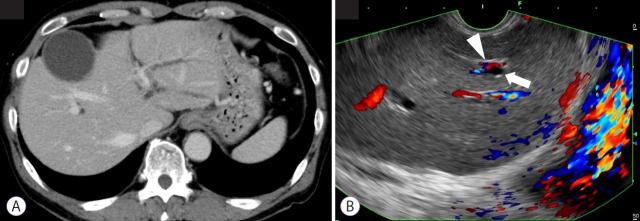

Endoscopic ultrasound (EUS)-guided hepaticogastrostomy (HGS) is widely performed not only as an alternative to transpapillary biliary drainage, but also as primary drainage for malignant biliary obstruction. For anatomical reasons, this technique carries an unavoidable risk of mispuncturing intrahepatic vessels. We report a technique for troubleshooting EUS-guided portal vein coiling to prevent bleeding from the intrahepatic portal vein after mispuncture during interventional EUS. EUS-HGS was planned for a 59-year-old male patient with unresectable pancreatic cancer. The dilated bile duct (lumen diameter, 2.8 mm) was punctured with a 19-gauge needle, and a guidewire was inserted. After bougie dilation, the guidewire was found to be inside the intrahepatic portal vein. Embolizing coils were placed to prevent bleeding. Embolization coils were successfully inserted under stabilization of the catheter using a double-lumen cannula with a guidewire. Following these procedures, the patient was asymptomatic. Computed tomography performed the next day revealed no complications.

摘要

内镜超声(EUS)引导下肝胃吻合术(HGS)不仅作为经乳头胆管引流的替代方法被广泛应用,还作为恶性胆管梗阻的主要引流手段。由于解剖学原因,该技术存在不可避免的误穿肝内血管的风险。我们报告一种用于解决EUS引导下门静脉盘绕的技术,以防止介入性EUS过程中误穿后肝内门静脉出血。计划对一名59岁不可切除胰腺癌男性患者行EUS-HGS。用19号针穿刺扩张的胆管(管腔直径2.8mm),并插入导丝。探条扩张后,发现导丝位于肝内门静脉内。放置栓塞线圈以防止出血。使用带导丝的双腔套管在导管稳定的情况下成功插入栓塞线圈。经过这些操作,患者无症状。次日进行的计算机断层扫描显示无并发症。